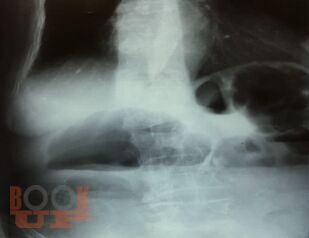

Острая кишечная непроходимость

В предлагаемом учебном пособии представлены вопросы классификации, диагностики и лечения острой кишечной непроходимости.